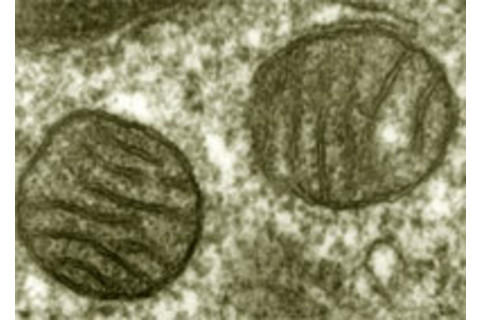

我们所有的细胞都含有称为 线粒体 的小型能量供应结构。它们是我们祖先细胞吞噬和驯化的古老细菌的后代。它们已经走得很远,但它们仍然保留着足够的细菌特征,一旦它们逃离了细胞的家园,就会让我们的免疫系统感到困惑。例如,受伤会将它们释放出来。如果细胞破裂,线粒体碎片会被释放到血液中,包括 它们自己的 DNA 和 典型的细菌氨基酸。秦张(Qin Zhang)的研究表明,创伤患者血液中的这类分子水平远高于未受伤的人。我们的白细胞有哨兵蛋白,它们会附着在这些分子上,它们的出现(错误地)表明正在发生细菌入侵。

这项发现解决了医学上的一个谜团。严重受伤的人有时会经历一种称为 “全身炎症反应综合征”或 SIRS 的剧烈且可能致命的反应,在这种反应中,炎症会遍及全身,器官开始衰竭。这与败血症非常相似,败血症是对感染的同样剧烈的反应。然而,挤压伤和烧伤会引起 SIRS,而没有伴随感染。现在我们知道了原因——SIRS 是由前细菌的碎片释放并引发了体内的虚假警报。这些体内敌人的技术术语是“损伤相关分子模式”或 DAMPs。